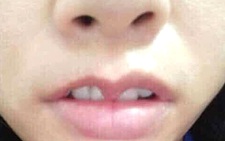

Sau khi nhổ răng, bà L. bị đau nhức kéo dài liên tục, kèm theo vùng nhổ răng xuất hiện sưng nề, chảy dịch, hơi thở xuất hiện mùi hôi rất khó chịu và mệt mỏi.

Ngoài viêm xương hàm, sau khi nhổ răng còn có thể gặp một số biến chứng như đau, viêm lợi, viêm huyệt ổ răng…